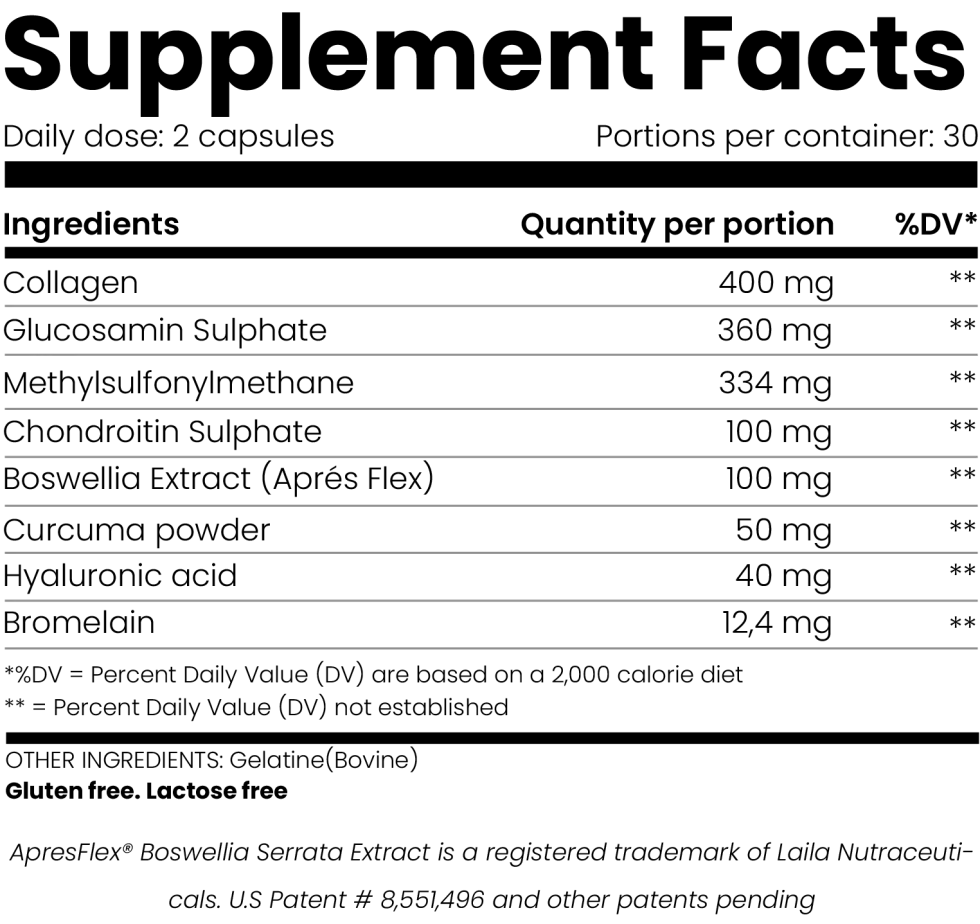

What is inside Opti Flex?

Contributes to mobility and joint lubrification. Helps keep joints healthy.

Helps to improve cartilage regeneration and nutrition. Promotes healthy bones and joints. Nourishes the joints and encourage the synthesis of collagen in the joint cartilage. Has a prositive effect on teeth, nails, hair and bones.

Helps maintain healthy joints and bones. Helps to relieve inflammatory pain. Used to aid disgestion. Helps maintain liver health. Helps maintain cardiovascular health. Helps keep skin healthy.

Helps keep joints soothed and comfortable. Supports joint suppleness.

Opti Flex contains only 100% natural and safe ingredients. The formula is tested for safety, quality and purity by an independent third party. There are to our knowledge no reported side effects. However, we recommend that you consult your practitioner before starting a new program.

Using Opti Flex is easy. Simply take 2 capsules a day. We recommend you take 1 capsule in the morning and one in the evening. You can also take all two capsules together with your largest meal of the day, if you prefer.